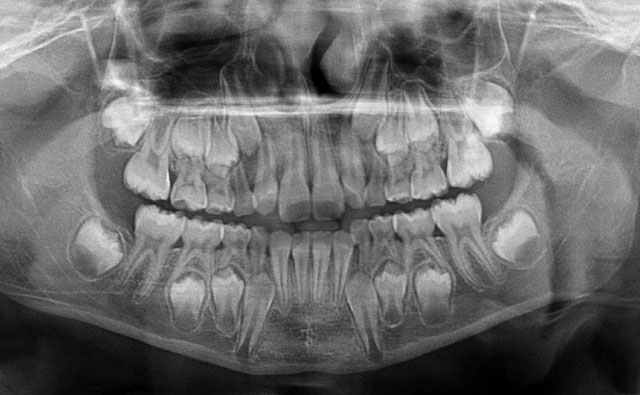

4.パノラマX-ray

パノラマサイズのレントゲンで、全部の歯を撮影することができます。

主に、親知らずの位置や、歯周病の進行状態を知る為、子供の歯の生え換わりの時期には永久歯の状態を知る為に撮ります。